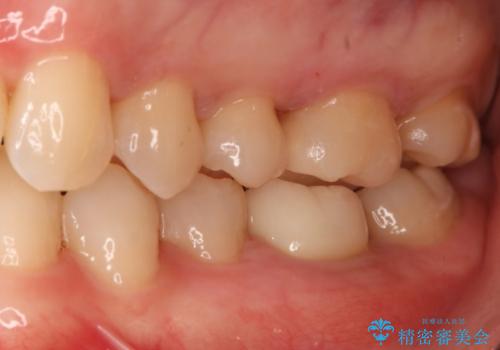

セラミックインレー修復 虫歯をとって白い歯へ

- 初診時、色が黒ずんでいる歯があり気になるとのことでいらっしゃいました。

診査の結果、下顎左右の前から6番目の歯に深い虫歯があったため治療をすることになりました。

歯の外形全体を削る必要性はなかったため詰め物(インレー)タイプで修復していく運びとなりました。(e-max プレスインレー)

虫歯=歯が痛い というイメージがある方も多いかもしれませんが、実際には時間をかけて少しずつ進行する虫歯は、無症状に歯の奥深くまで進行していることが多くあります。今回も歯の見た目の悪さを気にして来院されましたが、実際には神経の近くまで虫歯が広がっており、神経の治療が必要になる一歩手前の状態でした。早めの治療を行えたことで詰め物での治療で治すことができました。